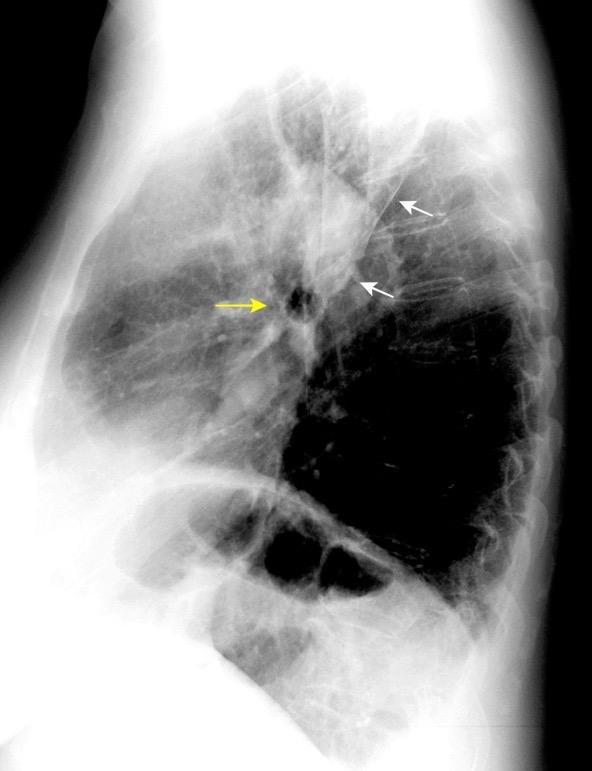

42. BRONQUIO LSI. ANATOMÍA

53. BPI .COMPRESIÓN Y DESPLAZAMIENTO HACIA ARRIBA DEL

¡Visualización buena!

Sospecha de ganglios aumentados, en el hilio derecho . Proto AV.1979

Sarcoidosis

Whitten CR. A Diagnostic Approach to Mediastinal Abnormalities. Radiographics 2007 / Marano R et al. Cardiac Silhouette findings And mediastinal lines and stripes. Chest. 2011

Anatomía

BPI: 75% de normales

La imagen es probable que represente al BPI, a la altura del nacimiento del BLSI.

AV,. The left lateral radiograph of the chest. Part One. Med. Radiogr. Photogr.1979.

La presencia de tumor o ganglios rodeando el BPI hace que este aparezca como mucho más nítido y definido.

Carcinoma microcítico..

Parálisis frénica. Atelectasia parcial de LSI.